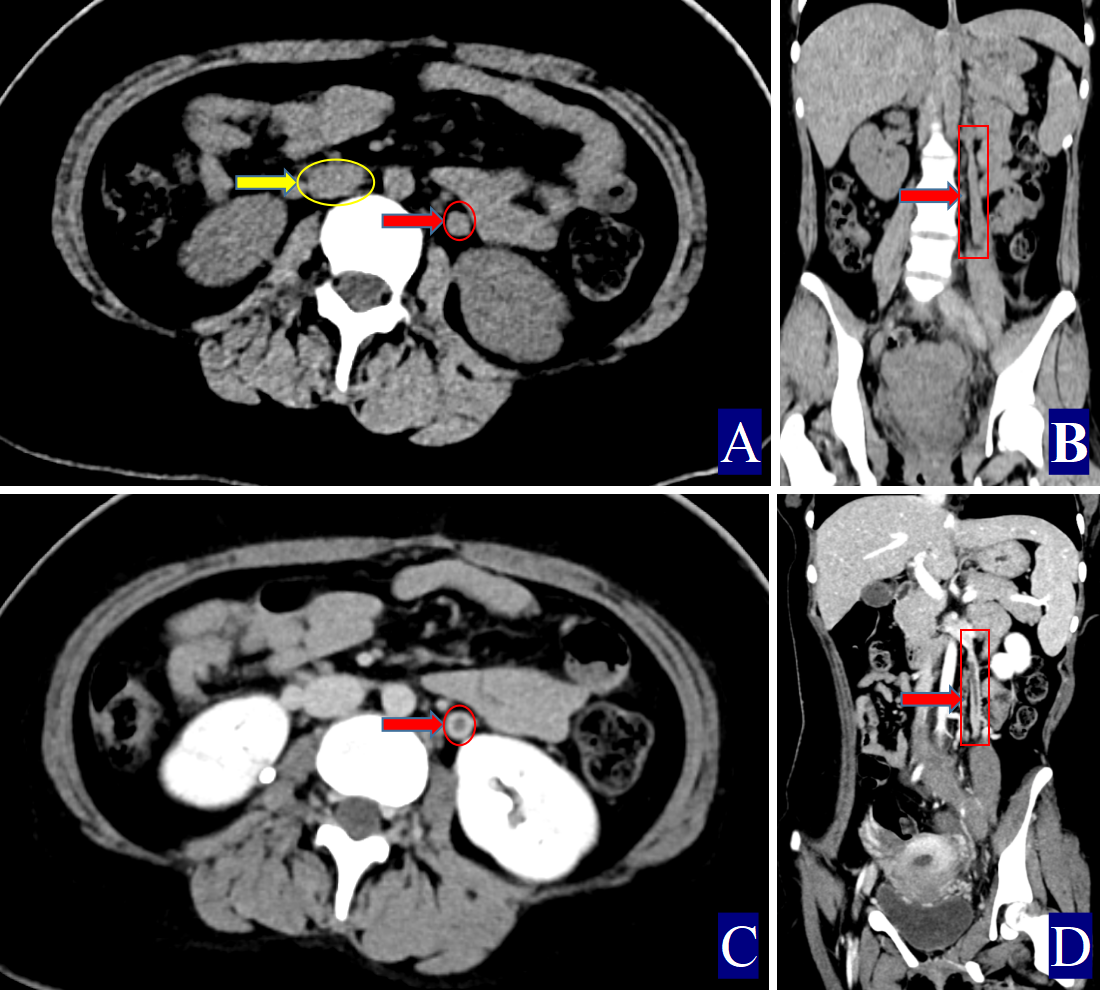

Fig. 2. A 17-year-old woman with left ovarian vein thrombophlebitis. The red color (red circle, red arrow and red cuboid) indicates the ovarian vein, the yellow color (yellow circle and yellow arrow) indicates the inferior vena cava. (A) Non-contrast axial CT image. The right OV measures approximately 0.91 cm in width (CT value = 46.10 HU, red arrow). The CT value of the inferior vena cava is 32.00 HU (yellow arrow). (B) Non-contrast coronal CT image showing the left OV (red arrow). (C) Contrast-enhanced axial CT image. Thrombosis in the left OV with uniform wall thickening (red arrow). (D) Contrast-enhanced coronal CT image. Left POVT with uniformly thickened wall (red arrow).

The primary CT findings of POVT included filling defects within the ovarian vein lumen along with thickening of the vessel wall (Figs. 1,2,3). Secondary signs involved pelvic effusion in 13 cases and periovarian venous exudation with increased fat density in 19 cases (Figs. 1A,C,3A,C). One patient, who developed extensive thrombosis extending to both lower extremity veins, the inferior vena cava, and pulmonary arteries, died from postpartum hemorrhagic shock. The remaining 23 patients fully recovered.

Compared with the non-POVT group, the POVT group showed significantly greater ovarian vein width on the thrombus side, higher CT attenuation of the thrombus-side ovarian vein, as well as increased CT attenuation difference and ratios (p = 0.001, Figs. 1,2,3). Using 0.90 cm as the cut-off value for ovarian vein width, the sensitivity reached approximately 91.70%, with a specificity of 95.20% (Figs. 1A,2A,3A,C,D). With 46.00 HU as the threshold for ovarian vein CT value on the thrombus side, both sensitivity and specificity were 100% (Figs. 1A,2A,3A). For a CT attenuation difference cut-off of 12.50 HU, the sensitivity was 95.30%, and specificity remained 100%. Similarly, a ratio cut-off of 1.1 yielded a sensitivity of 95.30% and specificity of 100% (Figs. 1A,2A,3A).

Direct signs observed on CT included variable widening of the ovarian vein, increased intraluminal density, and filling defects, often accompanied by vessel wall thickening, which is in line with prior reports [16, 17, 18, 19, 20, 21] (Figs. 1,2,3). A notable finding in our study was the identification of previously undescribed indirect signs: increased fat density around the ovarian vein in the pelvis and the presence of small-volume pelvic effusion (Figs. 1A,3A–D). These signs may reflect the local inflammatory reaction associated with thrombophlebitis.

Semi-quantitative parameters from non-contrast CT scans revealed clear differences between the POVT and non-POVT groups. The thrombus-side ovarian vein width, CT attenuation of the thrombotic ovarian vein, the difference between ovarian and inferior vena cava CT values, and their ratio were all significantly higher in the POVT group (p = 0.001, Figs. 1,2,3). These parameters may serve as reliable diagnostic references. For instance, using 0.90 cm as the cut-off for ovarian vein width yielded a sensitivity of approximately 91.70% and a specificity of 95.20%. This supports earlier findings [5] that vein enlargement is a key feature of POVT (Figs. 1,2,3). A CT attenuation cut-off of 46.00 HU for the thrombotic ovarian vein achieved 100% sensitivity and 100% specificity (Figs. 1,2,3). Similarly, a CT attenuation difference threshold of 12.50 HU and a ratio cut-off of 1.1 also demonstrated strong diagnostic performance (Figs. 1,2,3). However, in one patient with extensive thrombosis of the inferior vena cava, the ovarian vein had a lower CT value than the cava, resulting in a negative difference (–12.50 HU) and a ratio of 0.83, reflecting variability in advanced or complex cases. Currently available non-invasive diagnostic tools for POVT include Doppler ultrasound (sensitivity 52%), magnetic resonance imaging (MRI) (92%), and contrast-enhanced multidetector CT (100%) [5]. The present study indicates that non-contrast CT semi-quantitative parameters can closely match the diagnostic accuracy of enhanced CT, while offering greater simplicity, lower cost, and avoiding the risks associated with contrast agent use.